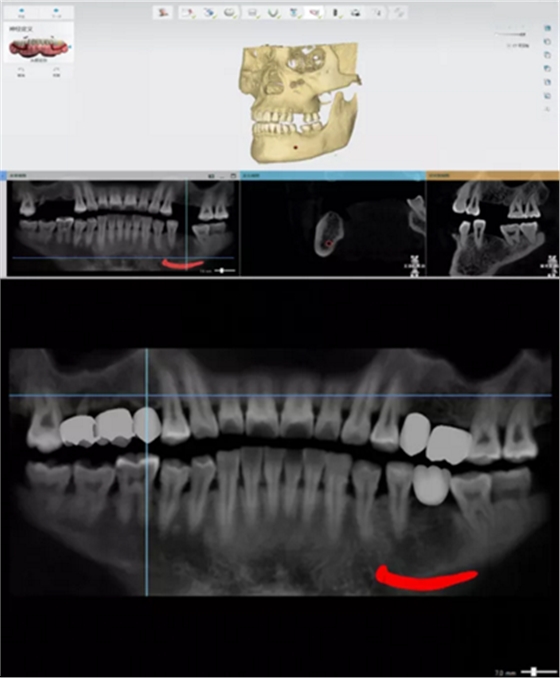

CBCT數(shù)據(jù)與模型數(shù)據(jù)整合

繪制下頜神經(jīng)管